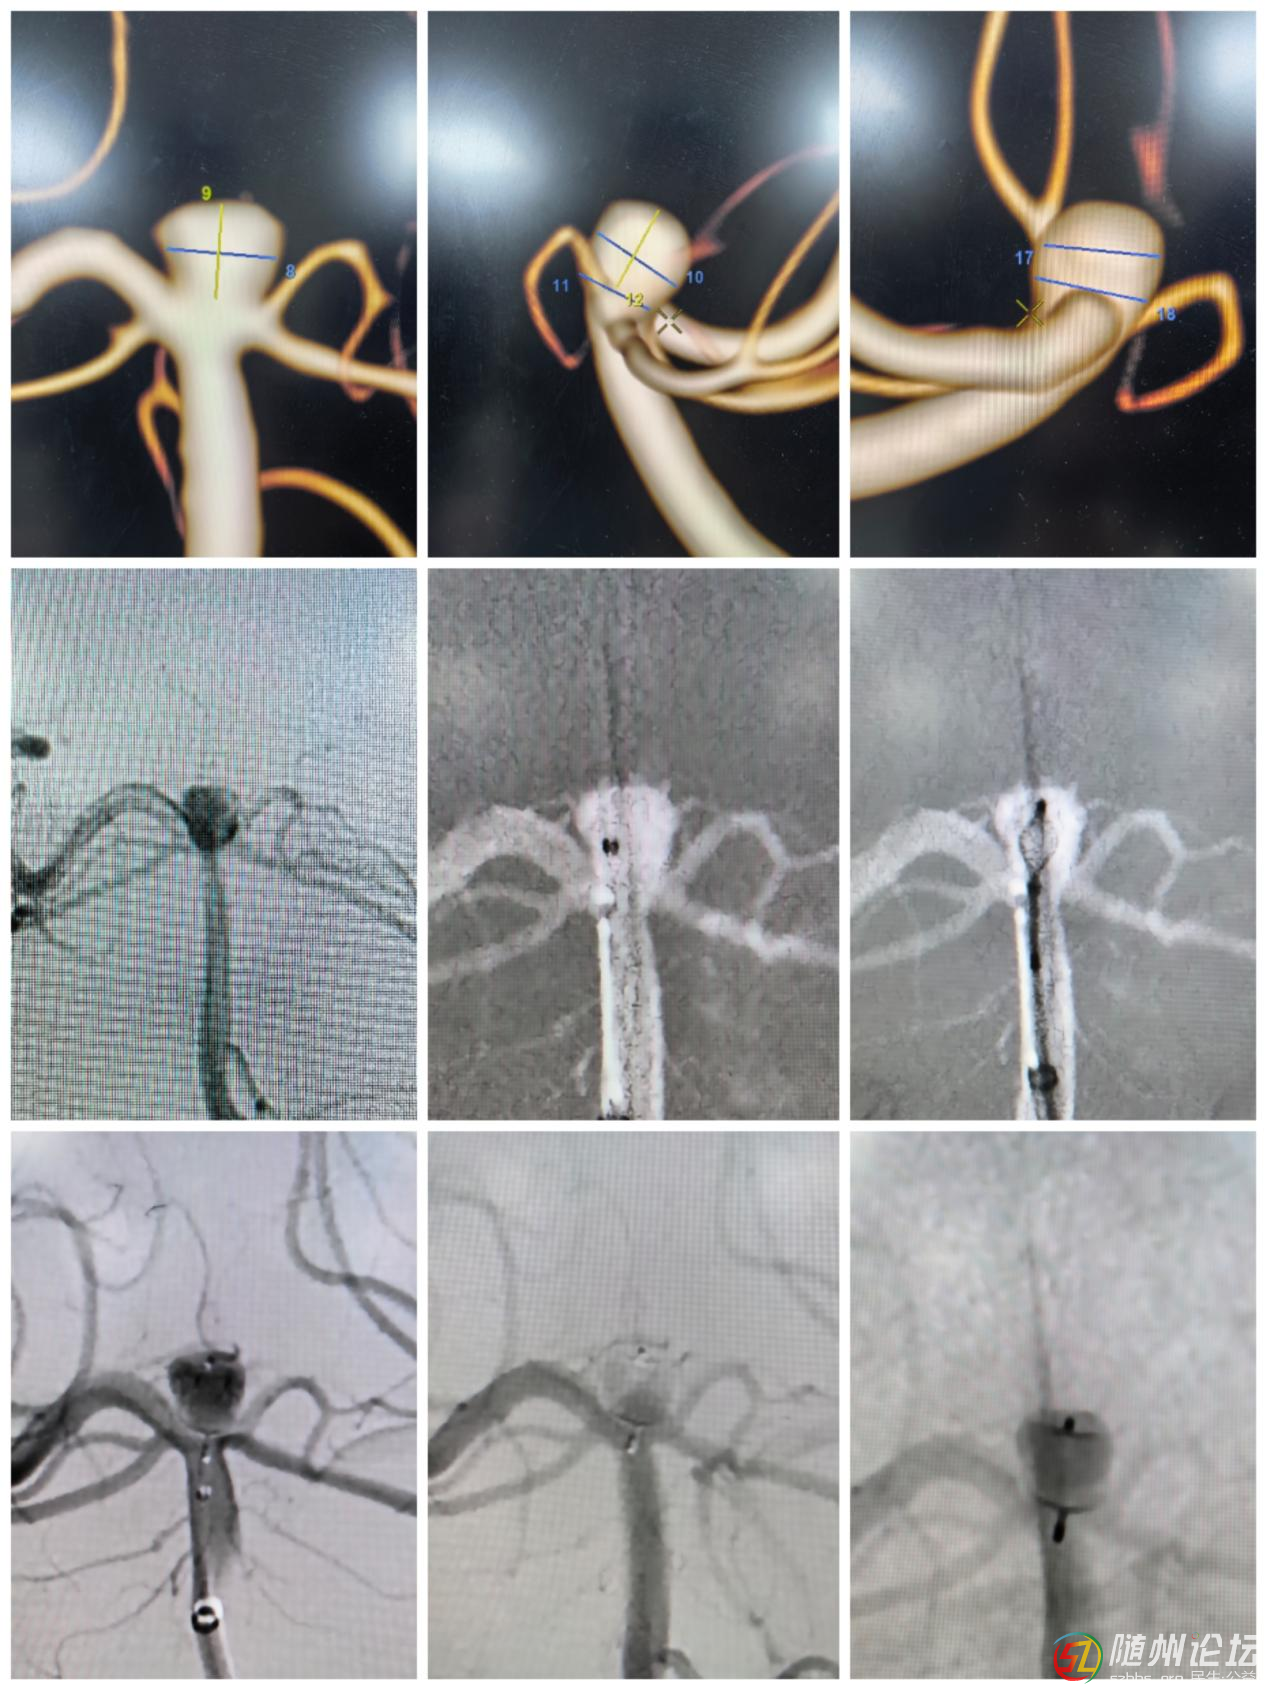

患者聶某(化名),66歲,一周前因頭暈、視物模糊就診,經(jīng)檢查發(fā)現(xiàn)基底動脈尖分叉部有一寬頸動脈瘤。該位置解剖結(jié)構(gòu)復雜,分支動脈多,傳統(tǒng)栓塞手術風險高、難度大,難以致密填塞并保留全部分支動脈。經(jīng)過多學科專家討論,團隊決定采用國際先進的WEB技術進行精準介入治療。

患者手術圖示

手術中,程偉主任醫(yī)師、黃豫軍副主任醫(yī)師通過介入方式將WEB裝置通過微導管置入動脈瘤腔內(nèi),利用其自膨脹網(wǎng)狀結(jié)構(gòu)即刻阻斷血流,避免瘤體破裂風險。整個手術僅耗時約1小時余,術后聶先生恢復良好,無神經(jīng)功能損傷,72小時后順利出院。